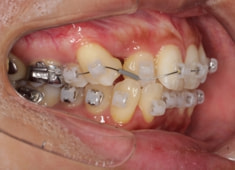

治療開始時